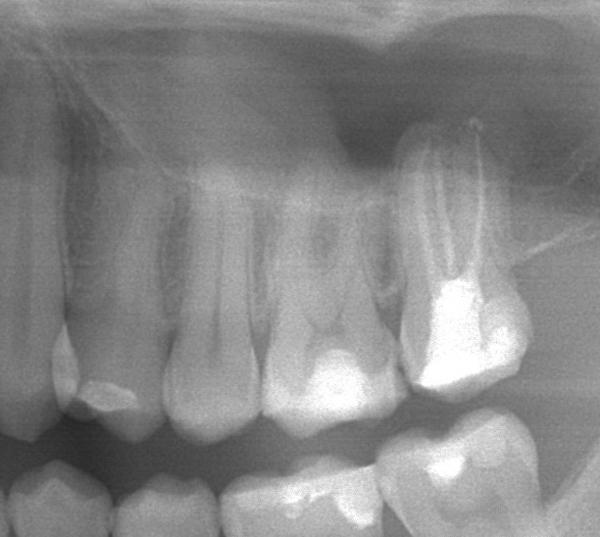

Der letzte Zahn links oben (27) soll im Rahmen einer Gebisssanierung mit einer Teilkrone versorgt werden. Die alten Wurzelkanalfüllungen (alio loco) sind etwas zu kurz und nicht homogen. Zudem war der Zahn nicht suffizient und bakteriendicht, sondern mit einer undichten Plastikfüllung versorgt.

Ausgangsröntgen (OPG):

Wir haben die Wurzelkanalbehandlung revidiert und dabei den zweiten mesiobuccalen Kanal (mb2) und akzessorische Kanäle füllen können. Die Kanäle sind bis zu den Wurzelspitzen vollständig gefüllt.

In der nächsten Sitzung wird der Zahn mit einer Keramikteilkrone versorgt. Die Prognose ist dann günstig.